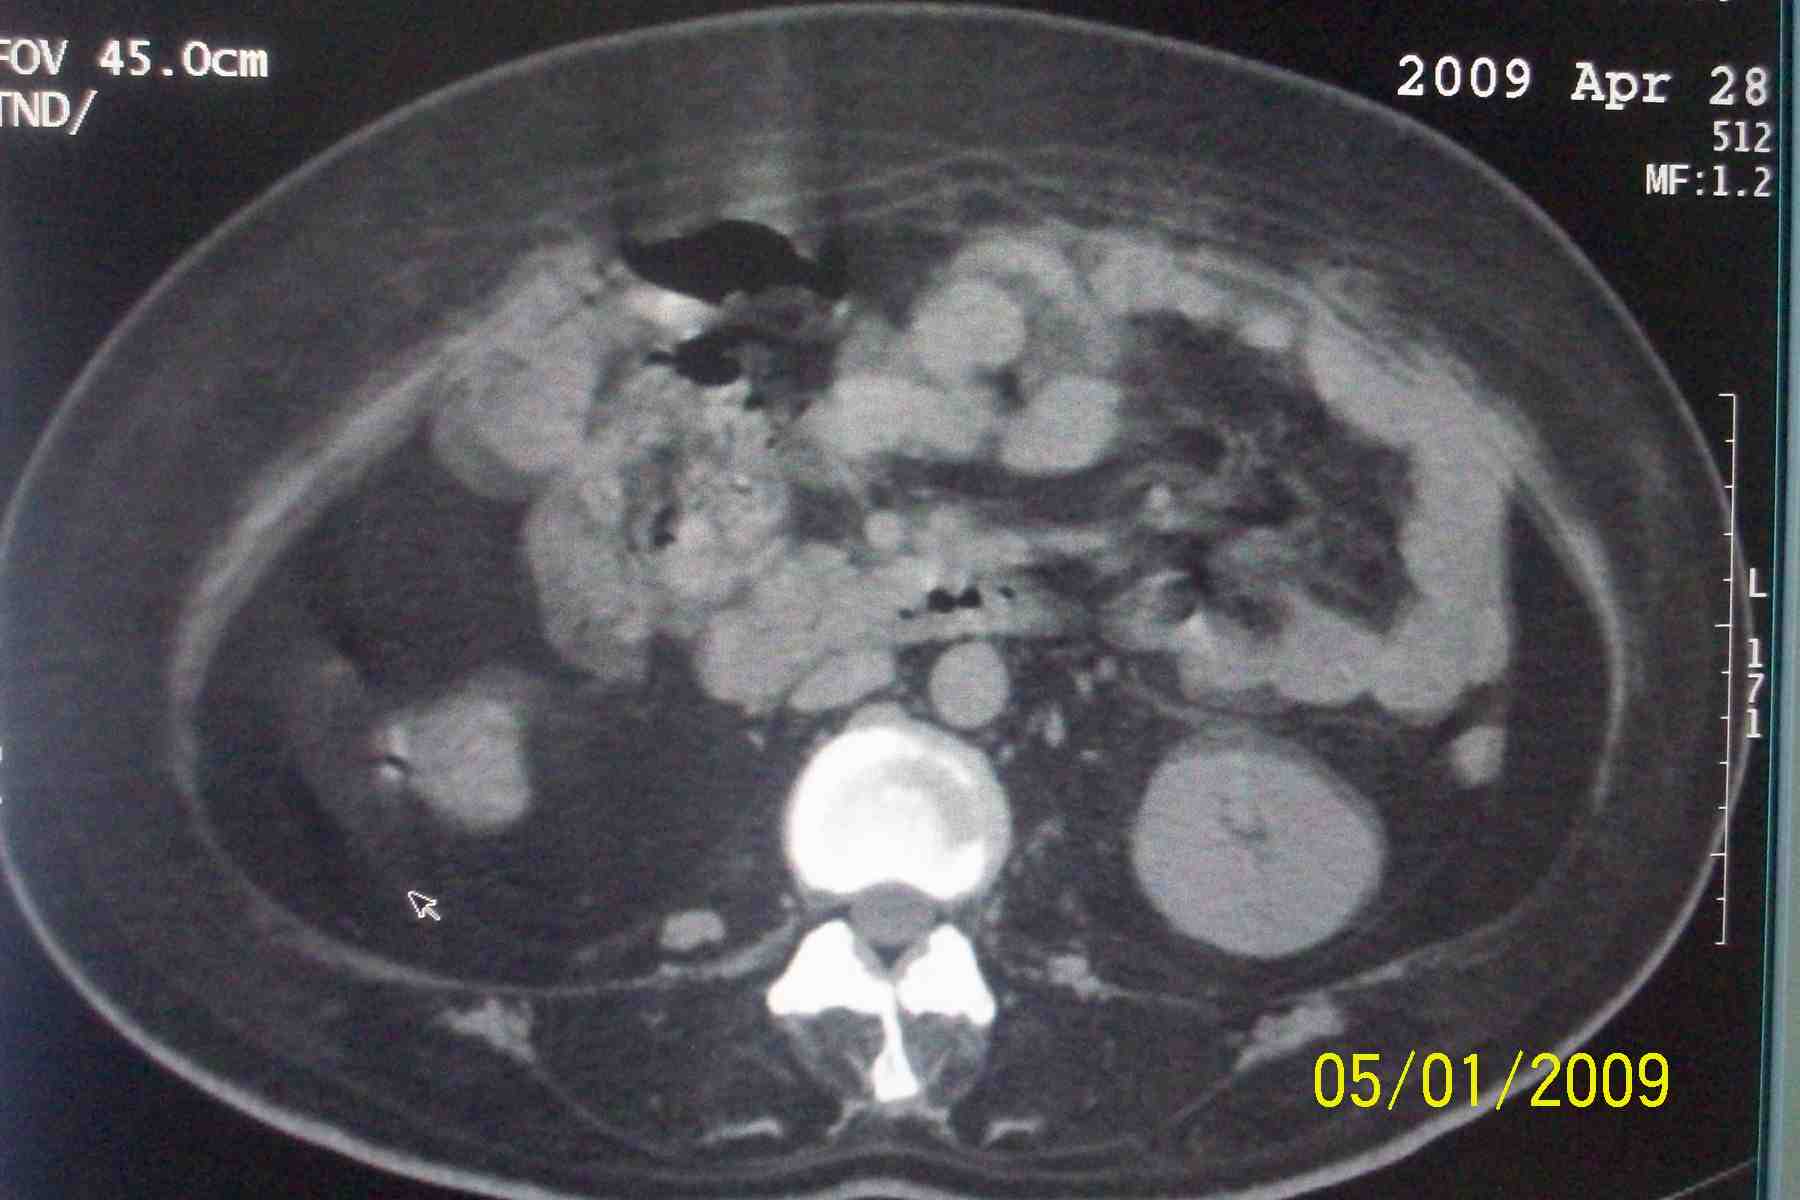

以下是引用杀毒软件在2009-5-1 17:43:00的发言:[br]良性对称性脂肪增多症

以下是引用ncy888888在2009-5-1 17:39:00的发言:[br]肾怎么弄丢了一个。